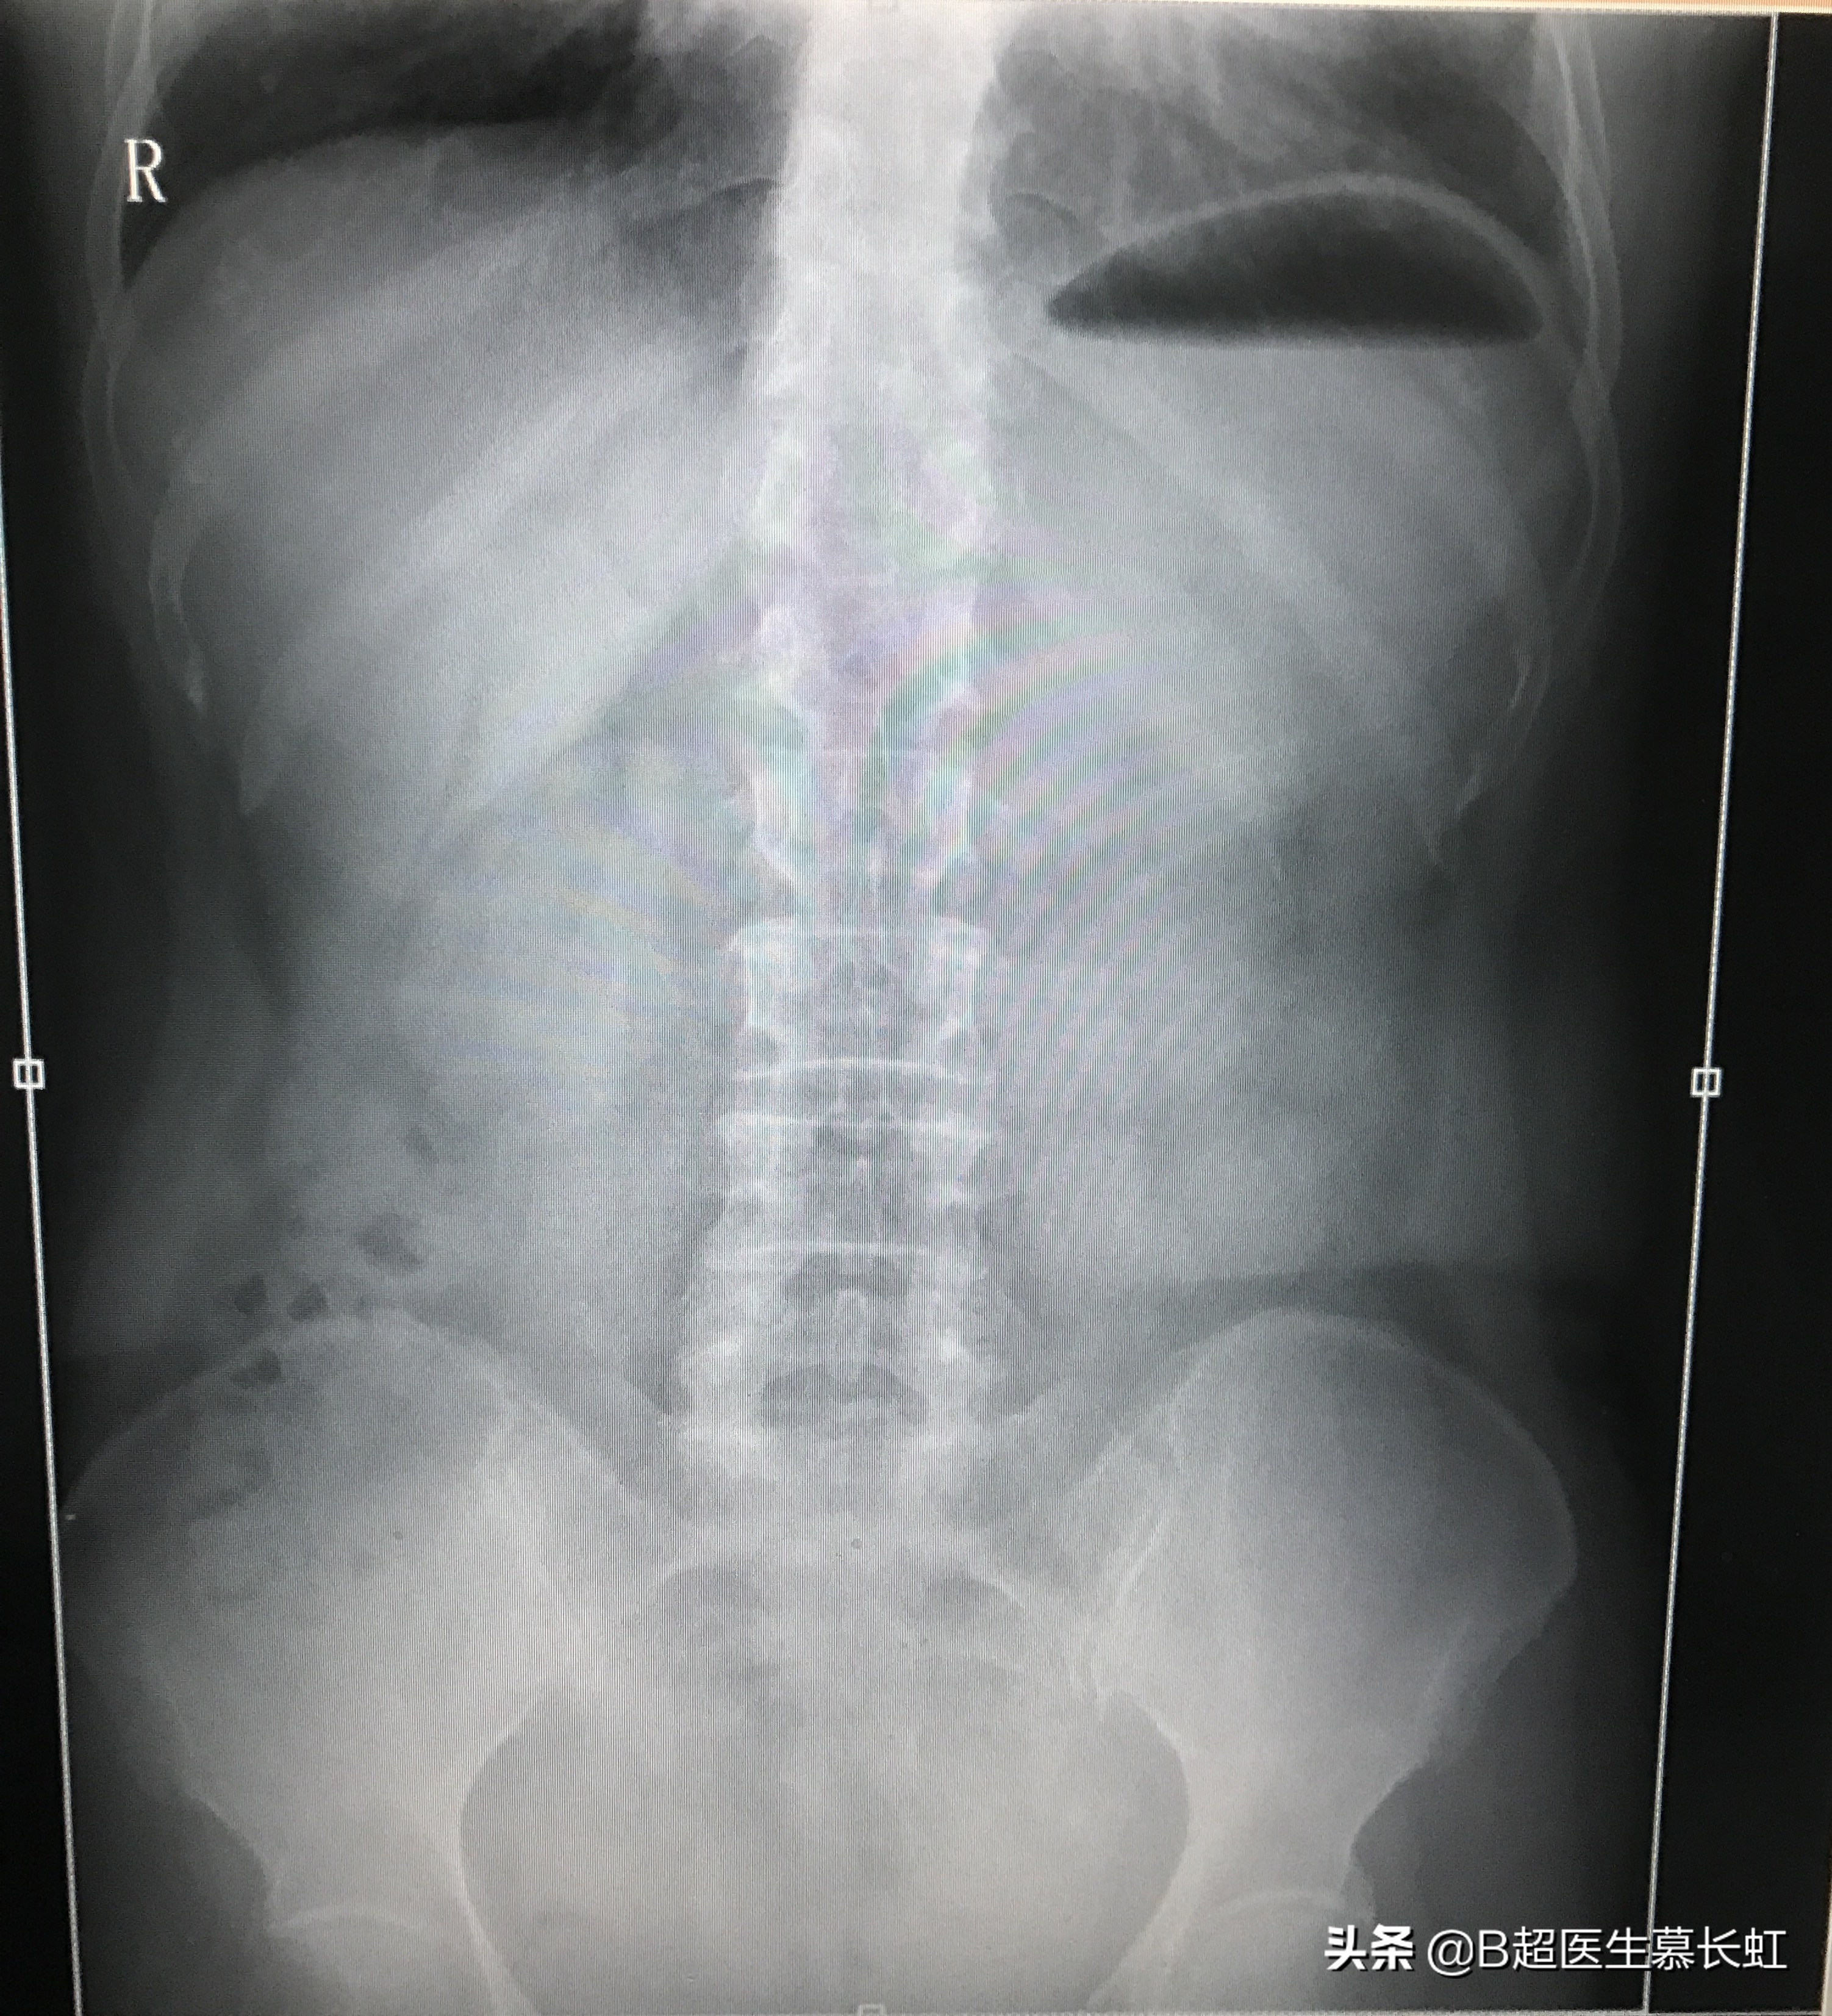

而消化内科医生说,X光片上并未发现肠梗阻的典型征象啊,而肠梗阻的诊断,必须是X光片上看到气液平才可以下肠梗阻的诊断。

患者的X光片

我也找来患者的X光片看,确实没有明显的气液平,但我的超声图像上看,确实已经很明显的肠梗阻表现了,我拉着消化内科医生到我的超声诊室里面,我亲自当场扫描给医生看,给她讲解超声图像,她看后相信了,也分析出了患者为什么会得肠梗阻了。